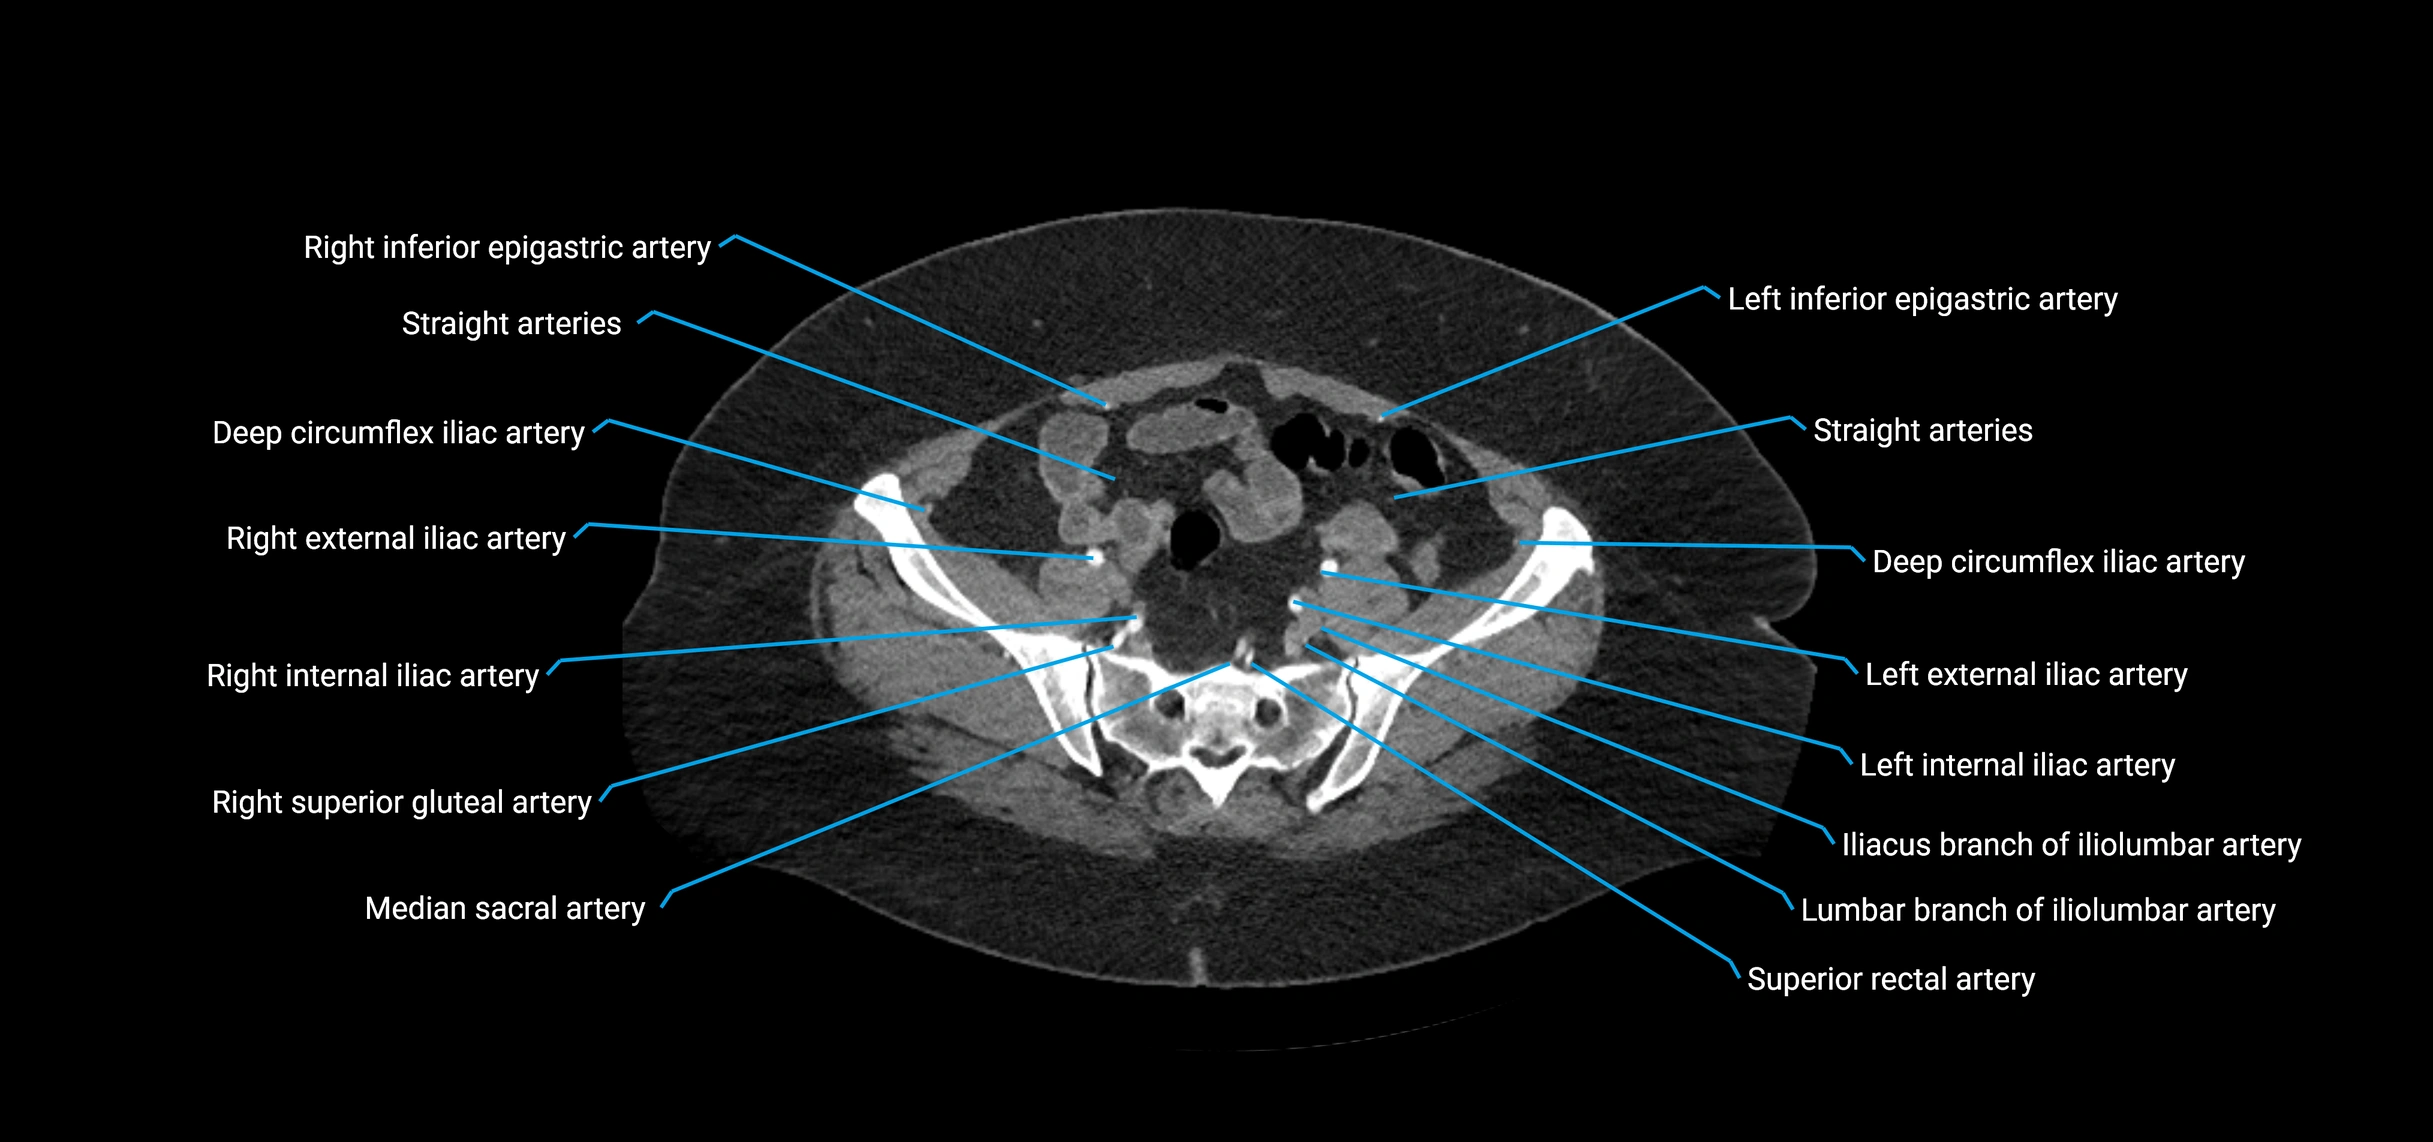

The abdominal aorta is the continuation of the thoracic aorta, beginning at the level of the aortic hiatus of the diaphragm (T12 vertebra) and terminating at the level of the L4 vertebra where it bifurcates into the right and left common iliac arteries. It lies slightly to the left of the midline and courses anterior to the vertebral bodies, surrounded by the retroperitoneal structures of the abdomen.

The abdominal aorta gives off numerous visceral and parietal branches, supplying the abdominal organs, pelvic structures, and lower limbs. It is the main conduit of oxygenated blood from the heart to the abdomen and lower body. The aorta is clinically significant as the common site of aneurysm, dissection, atherosclerosis, and traumatic injury.

Branches

• Parietal branches: inferior phrenic arteries, lumbar arteries, median sacral artery

• Terminal branches: right and left common iliac arteries

Contrast-enhanced CT (CTA):

• Gold standard for abdominal aortic imaging

• Provides excellent detail of lumen, wall, aneurysm, thrombus, and branch vessels

• Multiplanar and 3D reconstructions help in aneurysm measurement, stent graft planning, and dissection evaluation

• Detects acute rupture, traumatic injury, or occlusion with high sensitivity